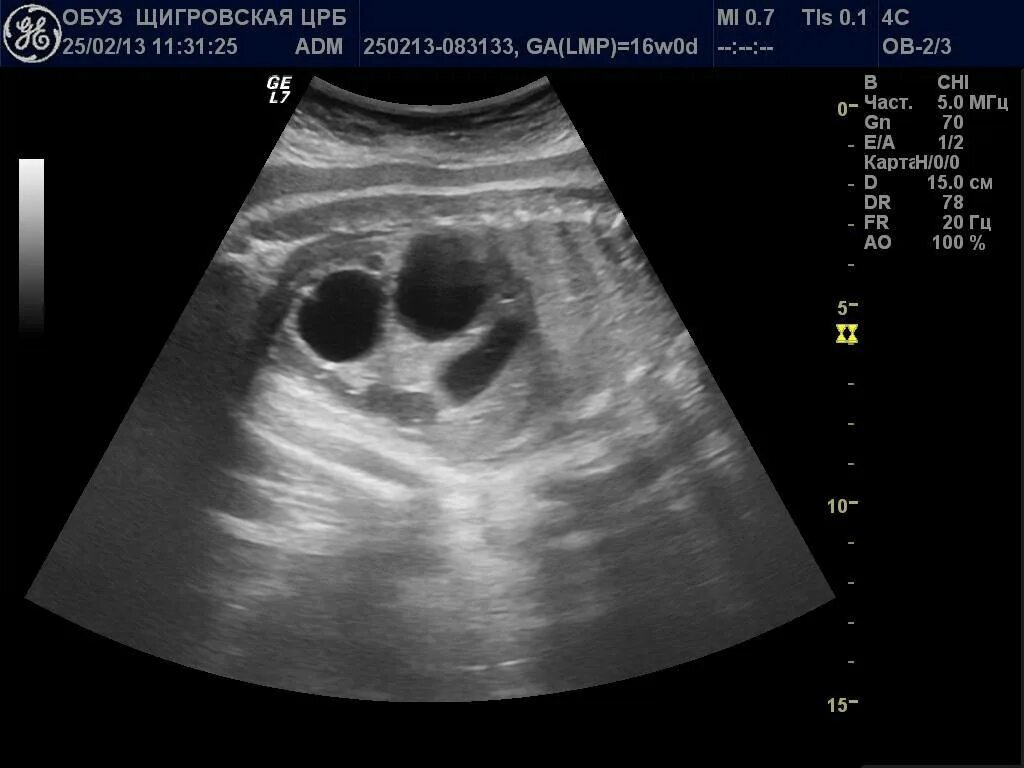

Мультикистозная почек плода